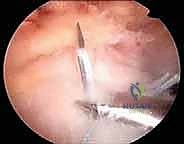

الخطوة 2: الاستكشاف بالمنظار (4K Arthroscopy)

يُحدث الدكتور هطيف 3 إلى 4 ثقوب صغيرة (بحجم ثقب المفتاح). يُدخل كاميرا دقيقة وعالية الوضوح (4K) لاستكشاف المفصل من الداخل. يتم تقييم حجم التمزق، جودة نسيج الوتر، والبحث عن أي إصابات مرافقة (مثل تمزق وتر البايسبس أو التهاب الجراب).

الخطوة 4: زراعة المثبتات وإصلاح مزدوج الصفوف

- الصف الداخلي: تُزرع مثبتات عظمية دقيقة (Anchors) محملة بخيوط جراحية فائقة القوة في الجزء الداخلي من البصمة العظمية.

- تمرير الخيوط: تُمرر هذه الخيوط عبر نسيج الوتر الممزق باستخدام أدوات دقيقة.

- الصف الخارجي: تُسحب الخيوط لتغطية الوتر فوق العظم، ثم تُثبت باستخدام مثبتات عظمية أخرى في الجزء الخارجي، مما يخلق شبكة محكمة تضغط الوتر بقوة ضد العظم.